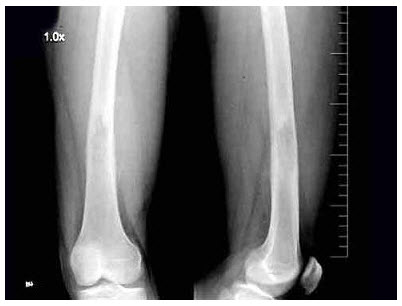

63、单项选择题

女,8岁,外伤后致右胫骨骨折,如图所示,下列描述正确的是()

A.对位好,对线差

B.对位差,对线好

C.对位对线好

D.对位对线差

E.以上均不正确